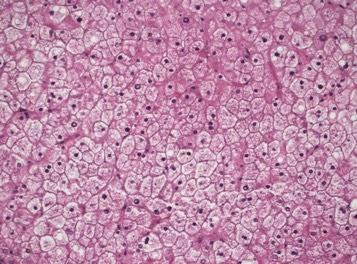

| Figure 1. Low power view showing pale liver parenchyma without steatosis or inflammation. |